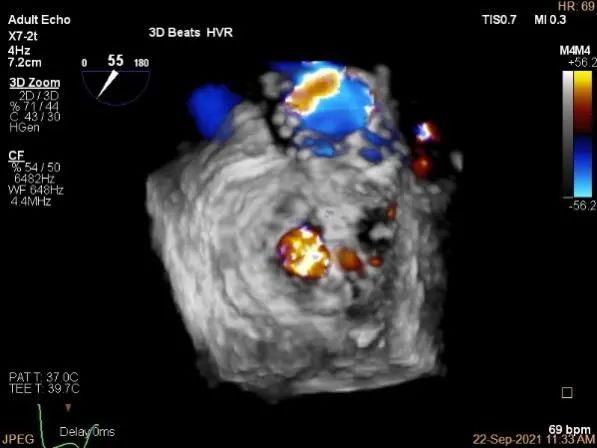

外侧残余少量分流

第一个夹子外侧残余小脱垂

残余分流主要来源于残余脱垂区域

评估瓣口条件,平均跨瓣压差:2mmHg,决定在第一个夹子外侧下第二个夹子

第一个夹子外侧放第二个夹子

第二个夹子捕获瓣叶后,前叶抓捕长度9.3mm,后叶抓捕长度7.3mm

未见明确残余分流